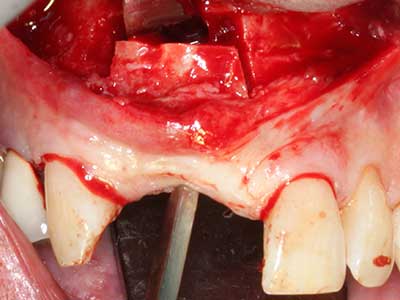

Preparation of the lateral window during an external sinus floor elevation is challenging, particularly for implantologists with little surgical experience. Removal of the bone cover of the sinus without injuring the underlying Schneiderian membrane is only part of the operation – after establishing an adequate access, the membranous lining of the sinus must be carefully mobilized to make space for the augmentation materials or the implants. Piezo surgery is useful for this indication in two ways: diamond-coated instruments can be used for selective bone ablation and the underlying mucous membrane remains intact when the procedure is done carefully. The ultrasonic frequencies also enable detachment of the mucous membrane without complications – the frequencies are transmitted into the space between the mucous membrane and sinus floor by special blunt attachments (Cassetta, Ricci et al. 2012, Pereira, Gealh et al. 2014) (Rickert, Vissink et al. 2013). As a result, it is not surprising that current reviews of external sinus floor elevation positively evaluate the use of piezoelectric devices as well as the use of roughened implant surfaces and bone replacement materials (Wallace, Tarnow et al. 2012).